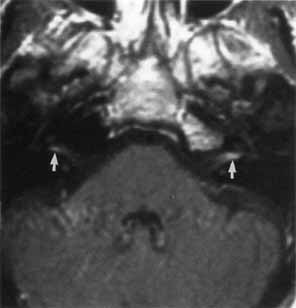

Lyme disease may cause unilateral or bilateral facial paralysis (Fig. 12).53 This disease is characterized by erythema chronicum migrans, tick-borne meningopolyneuritis, myocardial conduction abnormalities, and Lyme arthritis. The disorder was first recognized in 1975 by close geographic clustering of children with arthritis in the small community of Lyme, Connecticut. The spirochete B. burgdorferi is transmitted by an arthropod vector (the deer tick, Ixodes dammini). The skin lesion begins as a red macule or papule and expands to form a large red ring with partial central clearing. The lesion typically lasts about 3 weeks or longer (Fig. 13). Associated symptoms include malaise, fatigue, chills, fever, headache, myalgias, nausea, vomiting, and sore throat. Some patients develop a spectrum of neurologic symptoms and a clinical picture suggesting collagenosis, syphilis, or multiple sclerosis.

Fig. 12 Axial T1-weighted, gadolinium-enhanced MRI showing bilateral proximal facial nerve enhancement (arrows) in patient with Lyme disease and facial diplegia.

Cranial neuropathies occur frequently in Lyme disease; facial nerve palsy is the most common of these. Unilateral or bilateral facial nerve palsies occurred in 11% of patients with Lyme disease in one series.53 In the United States, facial palsy is observed in half the patients with Lyme meningitis. The prognosis for facial nerve recovery with or without therapy is excellent, with the majority of patients achieving satisfactory facial function. Despite the frequent spontaneous resolution of the facial paresis, therapy should be administered to prevent the late neurologic and arthritic complications that can occur. Interestingly, facial nerve paralysis occurs with or without CSF pleocytosis. Distinguishing Lyme-associated facial palsy from idiopathic (Bell's) palsy is essential. Lyme disease is suggested when there is coexisting multiorgan involvement such as cardiac disease or arthritis. Fever, enlarged lymph nodes, pharyngalgia, and headache are more common with Lyme disease than with Bell's palsy.54 Nontender swelling and erythema of the face before the onset of the facial palsy may also be a distinguishing feature of Lyme disease.55